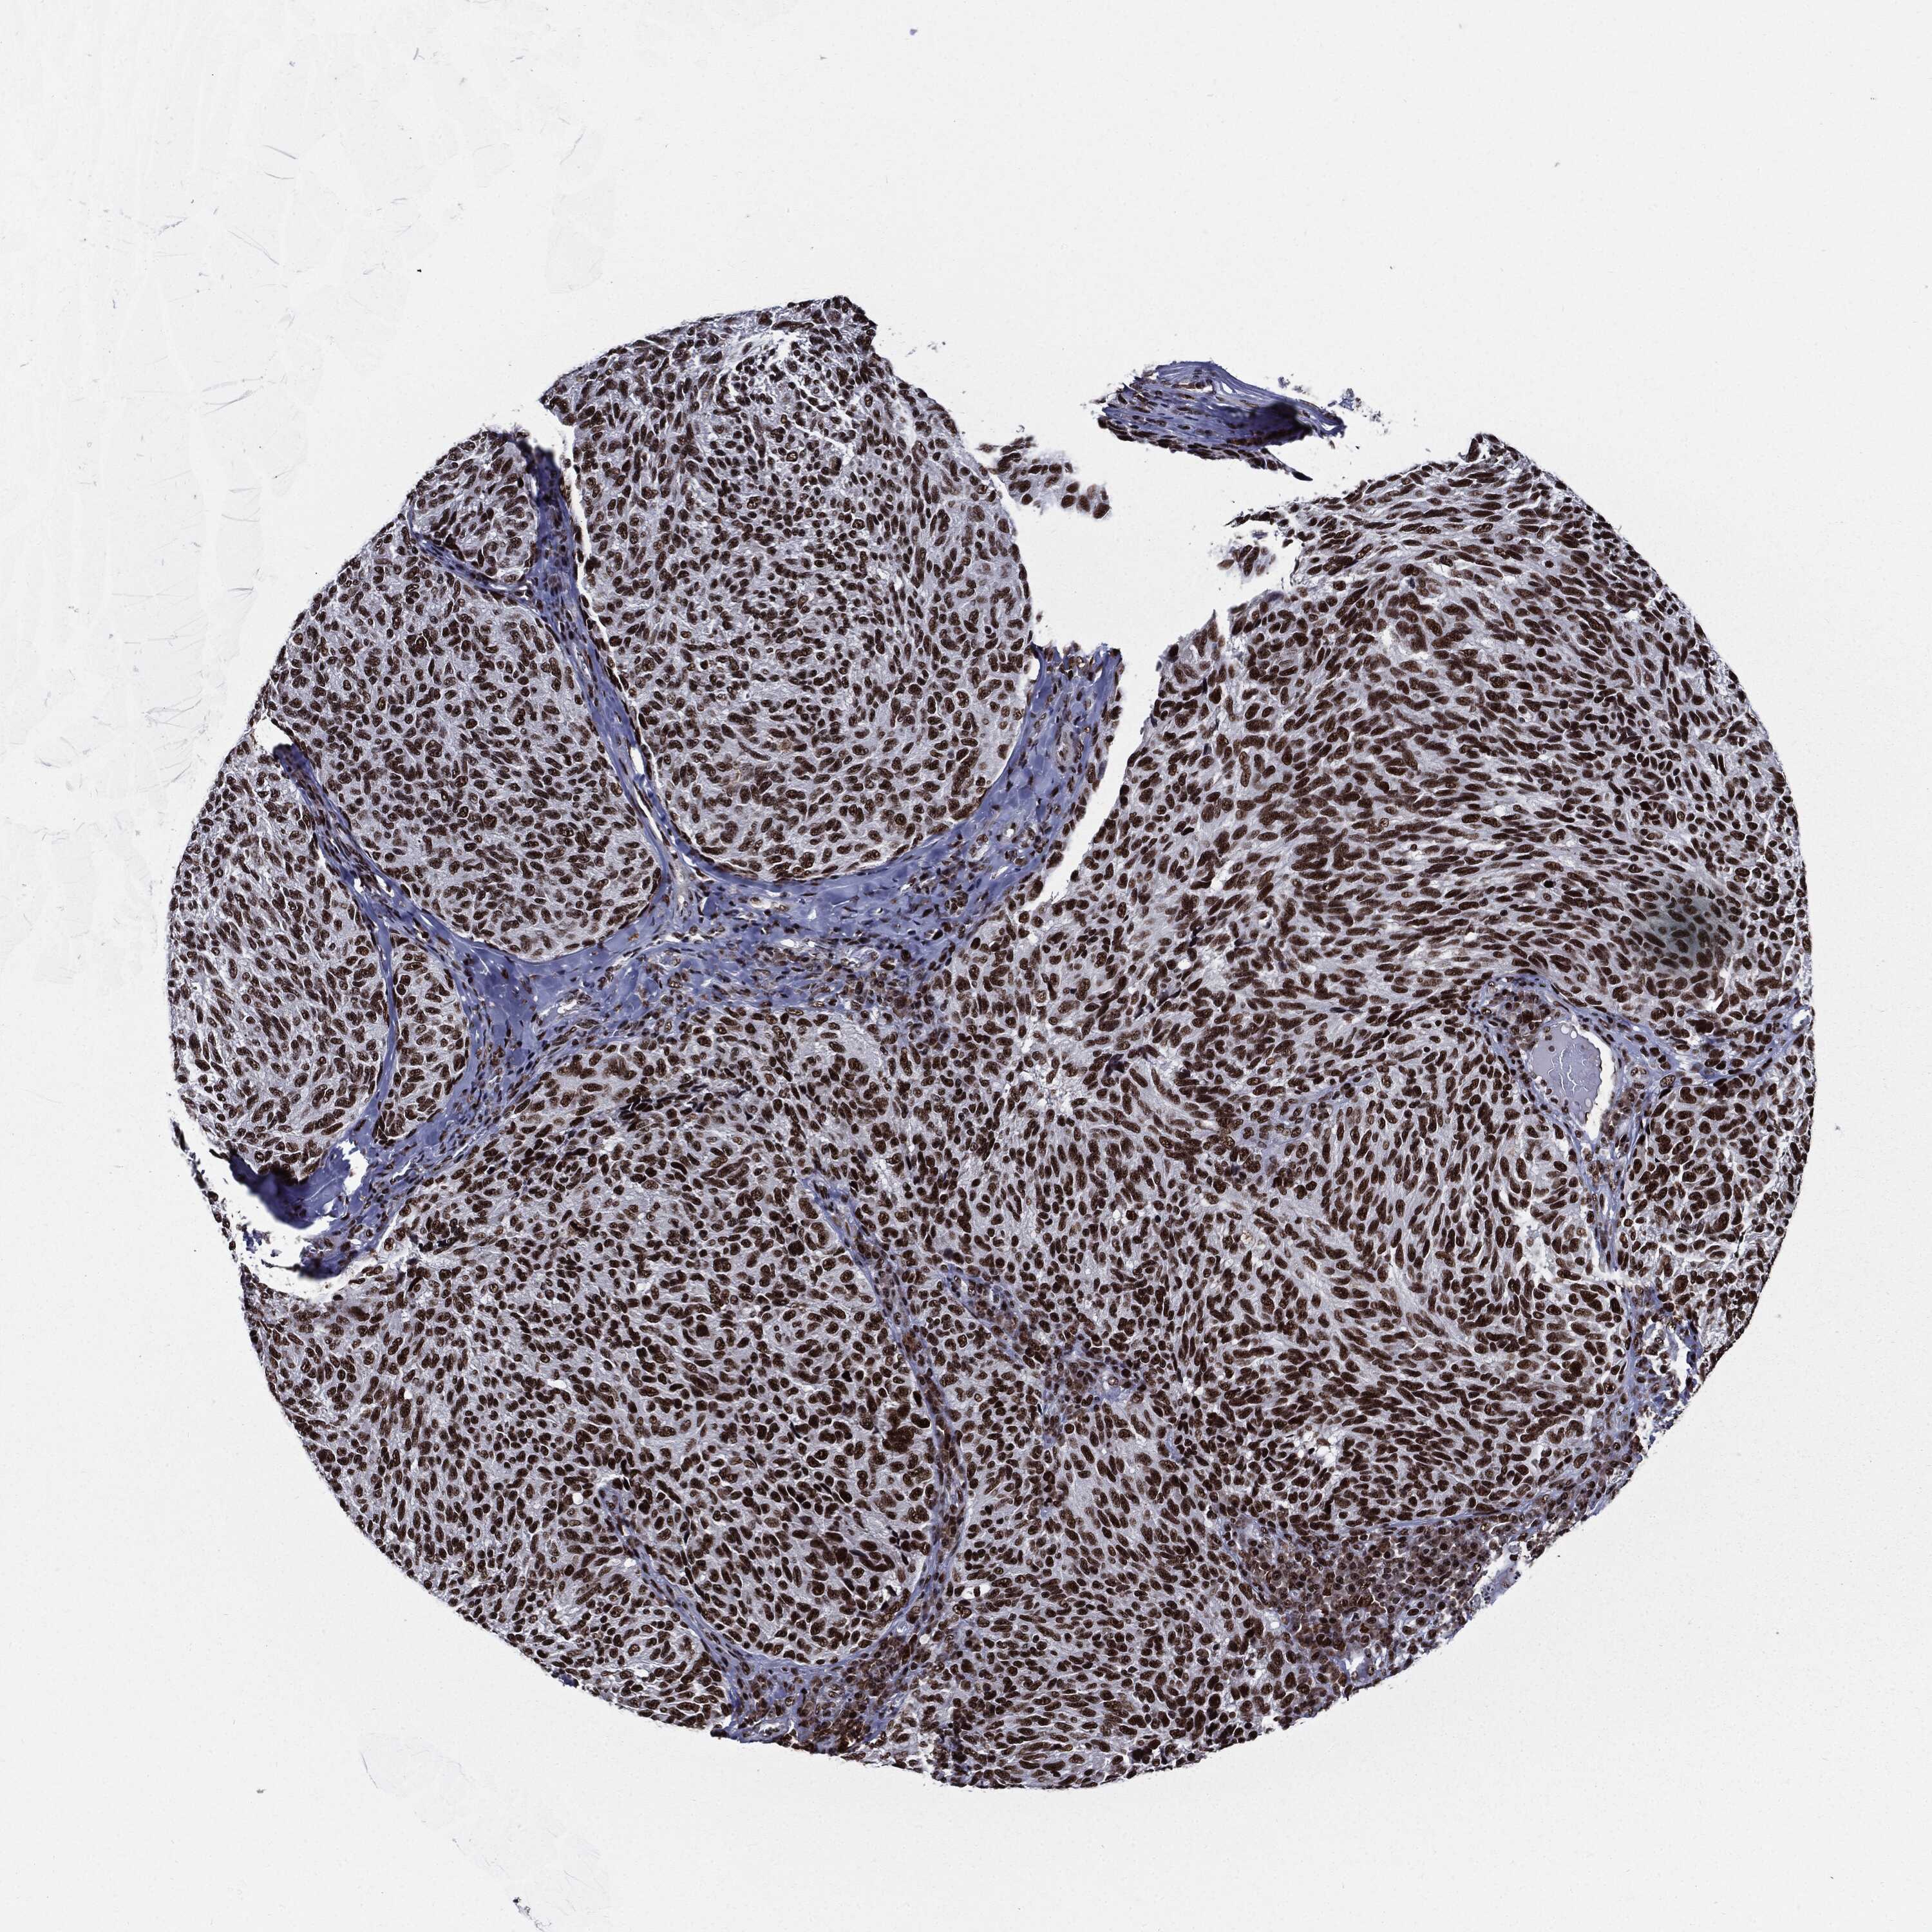

MELANOMA - Protein expressioni

A mouse-over function shows sample information and annotation data. Click on an image to view it in a full screen mode. Samples can be filtered based on level of antibody staining by selecting one or several of the following categories: high, medium, low and not detected. The assay and annotation is described here.

Note that samples used for immunohistochemistry by the Human Protein Atlas do not correspond to samples in the TCGA dataset.

Antibody stainingi

Antibody staining in the annotated cell types in the current human tissue is reported as not detected, low, medium, or high, based on conventional immunohistochemistry profiling in selected tissues. This score is based on the combination of the staining intensity and fraction of stained cells.

Each image is clickable and will lead to virtual microscopy that enables deeper exploration of all samples and also displays staining intensity scores, fraction scores and subcellular localization as well as patient and tissue information for each sample.

Antibody HPA024037

Antibody HPA065325

Antibody HPA074591

Antibody CAB025417

Malignant melanoma, NOS

Malignant melanoma, Metastatic site